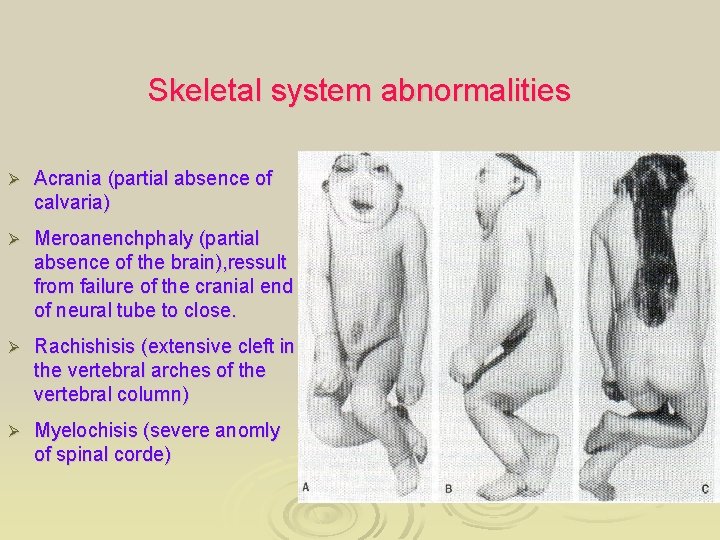

Skeletal system abnormalities Ø Acrania (partial absence of calvaria) Ø Meroanenchphaly (partial absence of the brain), ressult from failure of the cranial end of neural tube to close. Ø Rachishisis (extensive cleft in the vertebral arches of the vertebral column) Ø Myelochisis (severe anomly of spinal corde)